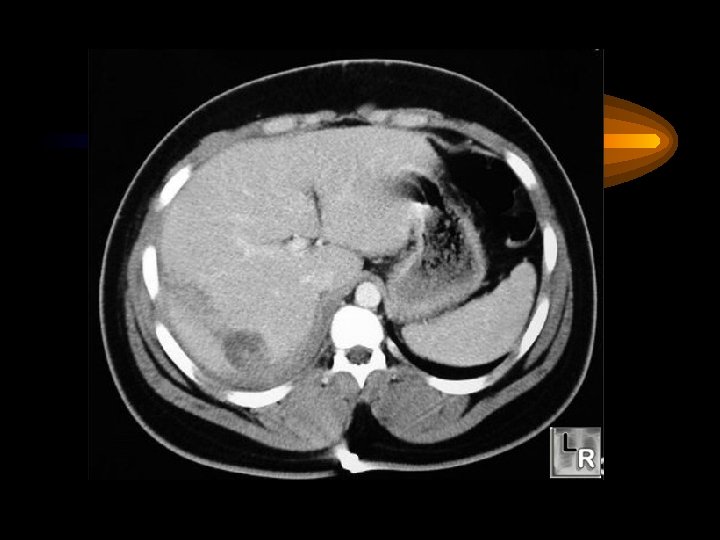

Pankreas Akut pankreatitis Karın ağrısı, bulantı-kusma, şok Nedenler Safra kesesi-yolları taşları Alkol Virüsler Hiperlipidemi, İatrojenik Tanı Serum amilazı yükselir Abd. CT ve US komplikasyonlar pseudokist, flegmon abse